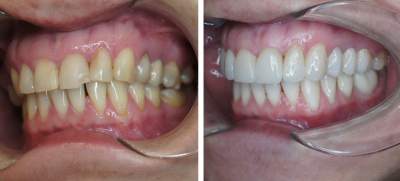

Gallery

Galeria